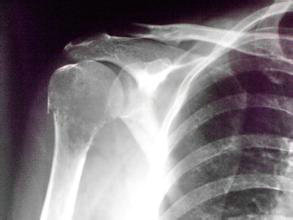

检查结果:血常规呈小细胞低色素性贫血;血沉140mm/h,C-反应蛋白22.3ng/ml;血钙2.13mmol/l,血镁1.66mmol/l,血磷正常,碱性磷酸酶289U/L;类风湿因子124IU/ml,CCP69.32RU/mL;关节放射片提示双手、双肩、双肘、双膝、骨盆骨质疏松,双肘及右膝关节半脱位改变。

(图:胡女士右肩治疗前照片)